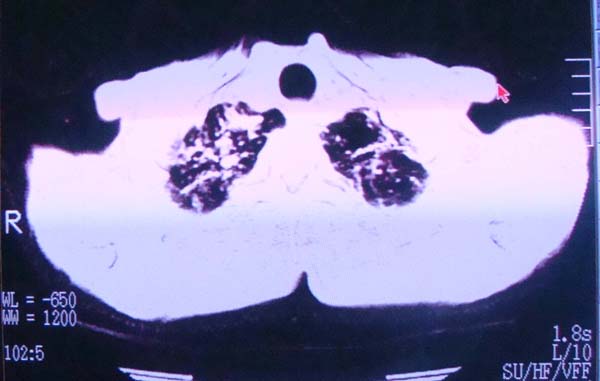

以下是引用zhangzhongshou在2008-2-15 22:25:00的发言:[br]片子照得不清,基本考虑1、细支气管肺泡癌2、亚急性血行播散型肺结核。请结合临床。片子细节显示不清,无法提供进一步意见。

以下是引用杀毒软件在2008-2-15 22:34:00的发言:[br]小叶中心性肺气肿。两肺弥漫性病变,肺泡微石病,过敏性肺炎,尘肺2期,特发性肺纤维化都有可能。[br]不象肺泡癌。